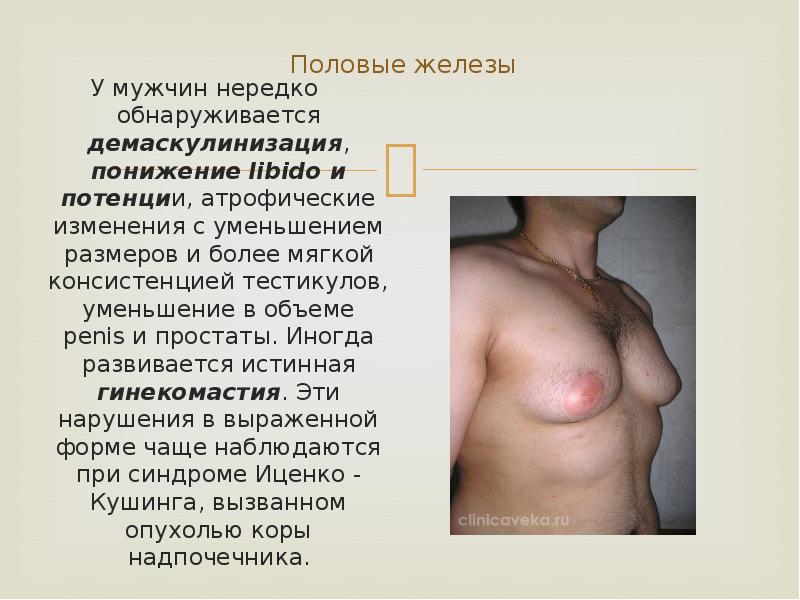

Половые железы

У мужчин нередко обнаруживается демаскулинизация, понижение libido и потенции, атрофические изменения с уменьшением размеров и более мягкой консистенцией тестикулов, уменьшение в объеме penis и простаты. Иногда развивается истинная гинекомастия. Эти нарушения в выраженной форме чаще наблюдаются при синдроме Иценко – Кушинга, вызванном опухолью коры надпочечника.